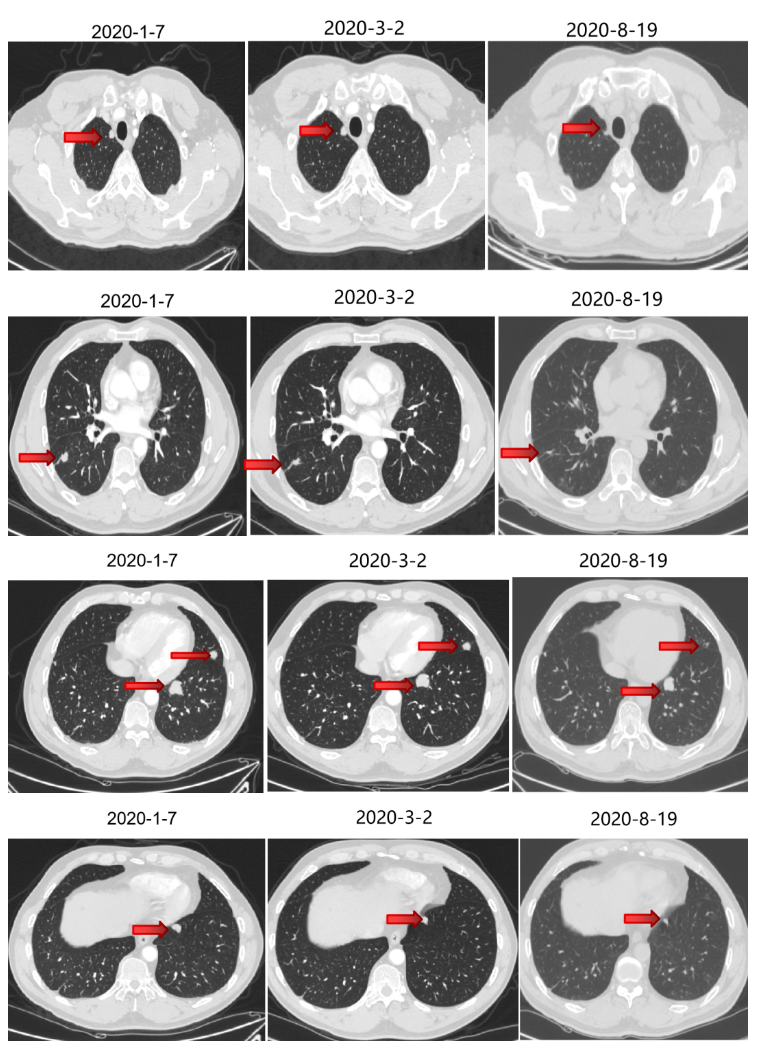

2020-1-8至2020-3-4 行4周期西妥昔单抗+FOLFIRI方案治疗,第2周期起联合曲妥珠单抗治疗。

2020-3-23至2020-7-28 予5周期贝伐珠单抗+曲妥珠单抗+伊立替康+卡培他滨(因菌血症输液港取出换用卡培他滨,因皮疹反应不耐受换用贝伐珠单抗)。

二线治疗疗效评价:部分缩小,SD。

维持治疗

2020-8-19至2020-10-22 予4周期维持治疗:贝伐珠单抗+曲妥珠单抗+卡培他滨。

维持治疗疗效评价:部分略大,SD。